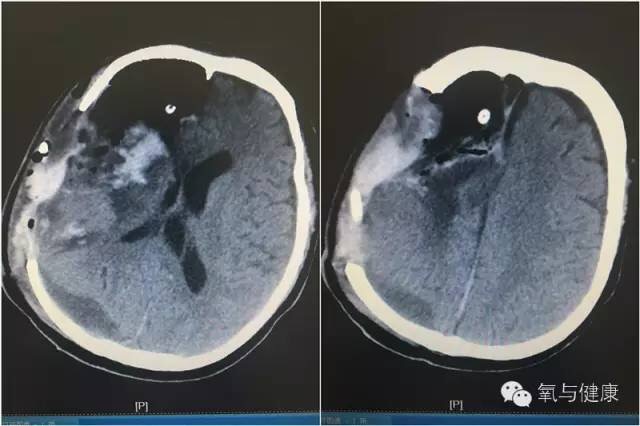

图2:四次手术后可见右大脑低密度伴出血、皮下血肿,合并颅内积气,中线左移,可见颅内引流管影

治疗体会:术后经历两次脑出血和一次术后伤口皮层下出血,高压氧治疗前,患者脑部影像提示右大脑低密度伴出血、伤口皮层下血肿,合并颅内积气,中线左移,病情危重。当时体温稍高,脑脊液蛋白升高,糖降低,是否又存在颅内感染呢?既往多次消化道出血病史,是否本身凝血功能欠佳?我们的会诊医师经仔细研读患者的病例,详细查看患者,综合考虑:1.患者生命体征尚平稳;2.凝血相基本正常,短期内再出血风险不大;3.高压氧治疗有助于减轻脑水肿、促进颅内血肿及积气吸收,将有效改善脑疝;4.即使存在颅内感染,高压氧治疗亦可促进抗生素药物透过血脑屏障,增强药效。决定:应积极尽早开始高压氧治疗。经详细与患者家属沟通,反复交待积极开展高压氧治疗的利与弊,在家属知情同意后,在医护人员陪护,患者生命体征持续监测下,每日1次的高压氧舱内抢救治疗。患者经连续高压氧治疗10余次后病情逐渐好转,无出血加重迹象,神经功能障碍明显改善,病情平稳后出院,转回患者家当地医院继续高压氧和康复治疗。(高压氧科 于秋红)